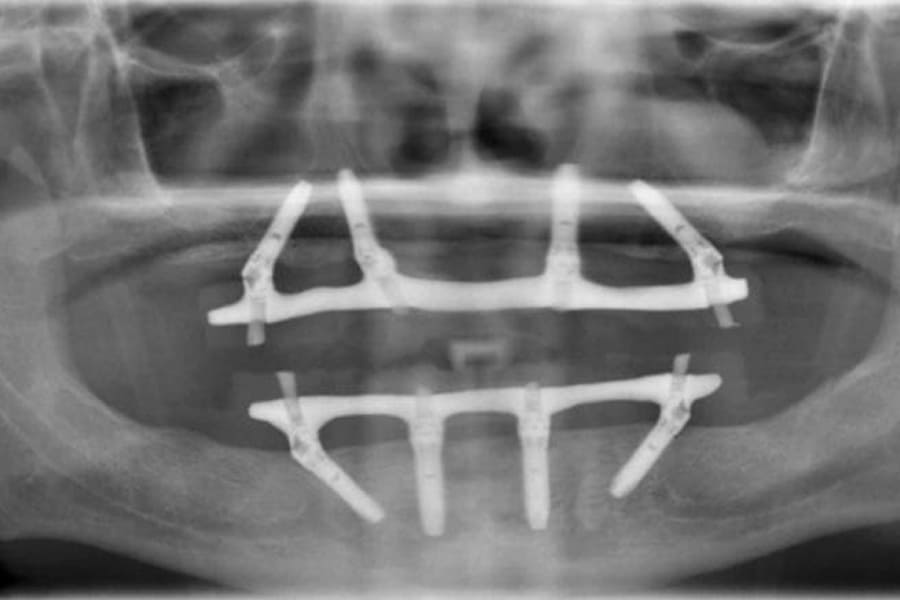

A prótese protocolo é uma estrutura fixa instalada sobre implantes dentários, indicada para pacientes que perderam todos os dentes superiores, inferiores ou ambos. Diferente das próteses móveis, ela fica fixada, o que promove estabilidade.

Esse modelo apresenta uma base metálica resistente que se adapta à arcada, permitindo função mastigatória igual aos dentes naturais. Por isso, é considerada uma “dentadura fixa” que renova o sorriso.

Em muitos casos, é possível realizar a prótese protocolo com carga imediata. Isso permite que o paciente saia da clínica com dentes definitivos fixos no mesmo dia da cirurgia de implantes. Essa técnica é indicada após avaliação minuciosa da saúde bucal, densidade óssea e estabilidade dos implantes.

Embora pareça um processo complexo, a sequência é bem estruturada e segura. Em geral, o tratamento envolve: